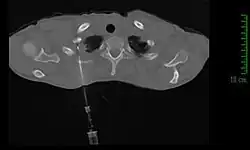

Modalités diagnotiques

Si la clinique et l'imagerie permettent à elles seules de poser le diagnostic de tumeur de Pancoast-Tobias, ce n'est que l'analyse d'une biopsie tissulaire qui permettra d'identifier le type de tumeur, et ainsi de guider le traitement[11].

La méthode de diagnostic la plus précise est la ponction percutanée trans-thoracique par ponction à l’aiguille, sous contrôle scanner, qui présente un rendement de 95 %[11],[21]. En cas d'échec, il est possible de réaliser une biopsie chirurgicale par thoracoscopie ou thoracotomie[11].